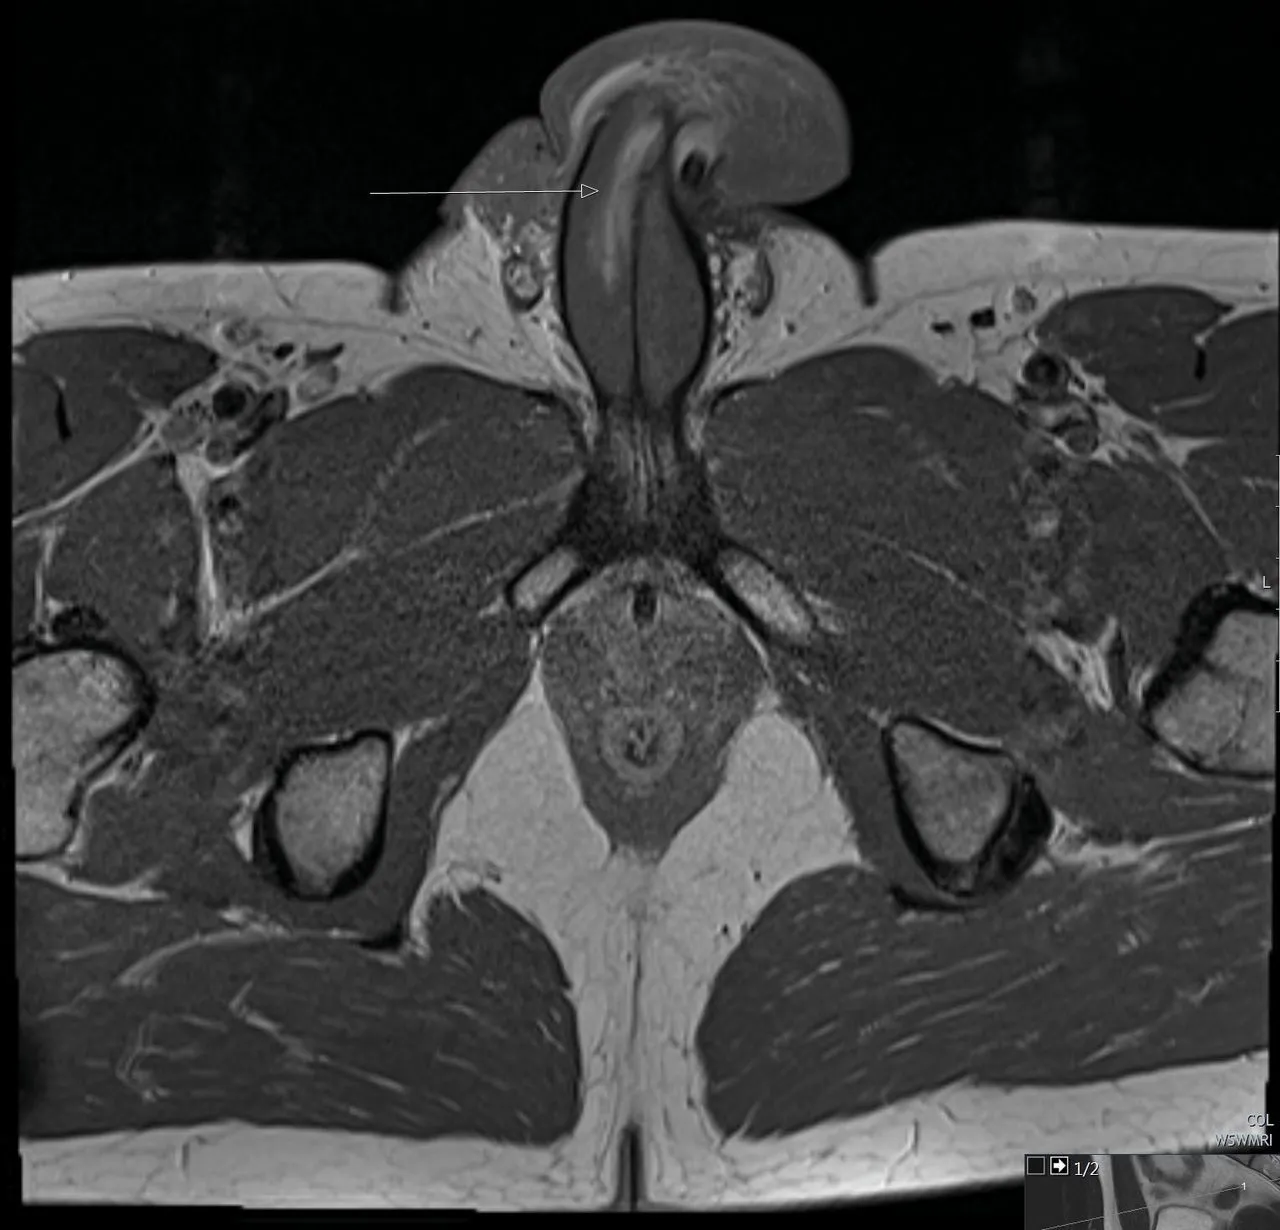

Au bout de six mois, les médecins ont fini par réaliser une IRM, qui a révélé leur erreur de diagnostic. Le quadragénaire présentait une rupture verticale de la tunique albuginée, autrement dit, une déchirure s’étalant sur 3 cm.

La radio partagée par la revue médicale British Medical Journal montre d'une flèche l'ampleur de la blessure.